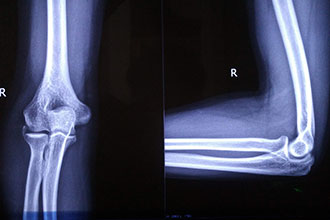

战略支援部队特色医学中心(原中国人民解放军第306医院)中医骨伤科副主任医师王光涛在接受人民网科普中国采访时介绍,骨软骨瘤是一种常见的多发于儿童和青少年时期的良性骨肿瘤,可分为单发性和多发性两种类型,通常前者比后者常见,且后者可能有遗传倾向。骨软骨瘤的形状通常类似于圆锥体,病情发展缓慢且症状不明显,大多数患者没有疼痛感,少数患者有轻微的按压痛或自发性疼痛,一般不影响患者的日常生活,患者通常因偶然摸到肿块或X线检查时而发现肿瘤。

王光涛表示,骨软骨瘤的形成应与骨骼的成骨过程联系在一起。在生长发育期,部分骨骼是通过软骨向骨质转变的过程来完成生长的,其中长管状骨在这类骨骼中占有较大比例,因而骨软骨瘤通常生长于长管状骨的骨端,膝盖上下多见,即股骨远端、胫骨近端较为多见。骨软骨瘤的生长依靠于软骨向骨质转变的过程,通常在患者发育成熟后会随着软骨的闭合而自动停止生长,同时骨软骨瘤发生恶变的几率非常低,通常为1%左右。而且目前临床上关于骨软骨瘤的发病原因还没有确切的定论,所以无法做相应的预防工作。

在发现患有骨软骨瘤后,患者应如何处理呢?王光涛介绍,骨软骨瘤不是一个特别复杂的疾病,患者无需过于担心。骨软骨瘤的唯一有效治疗方法就是通过手术进行切除,患者在发现患有骨软骨瘤后,可以通过手术进行切除,如骨软骨瘤没有任何症状或没有时间进行手术治疗时,也可以选择定期观察,即每半年到医院检查一次即可。